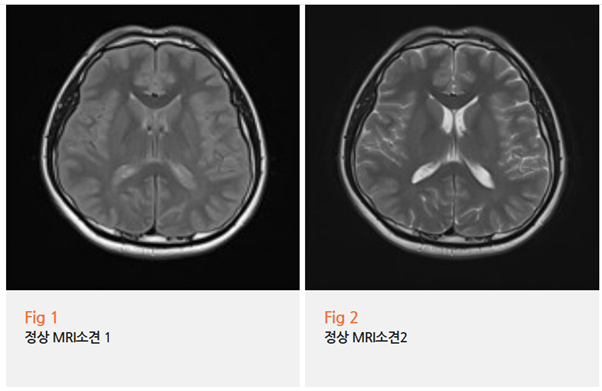

경동맥 초음파도 해보고, 뇌 MRI도 찍어봤는데

특별한 이상은 없다고 하니

본인으로서는 더 답답하셨을 것 같아요.

분명히 아픈데 원인을 모르겠다는 거잖아요;;

일반적인 MRI나 CT로는 잘 보이지 않거든요.

그런데 이런 미세한 변화는 영상 검사로는 찾아내기 어렵습니다.